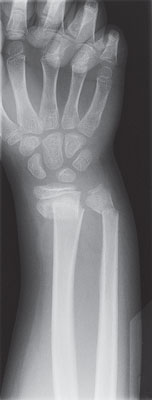

X-ray of an arm and hand showing a broken wrist

X-ray of a broken wrist